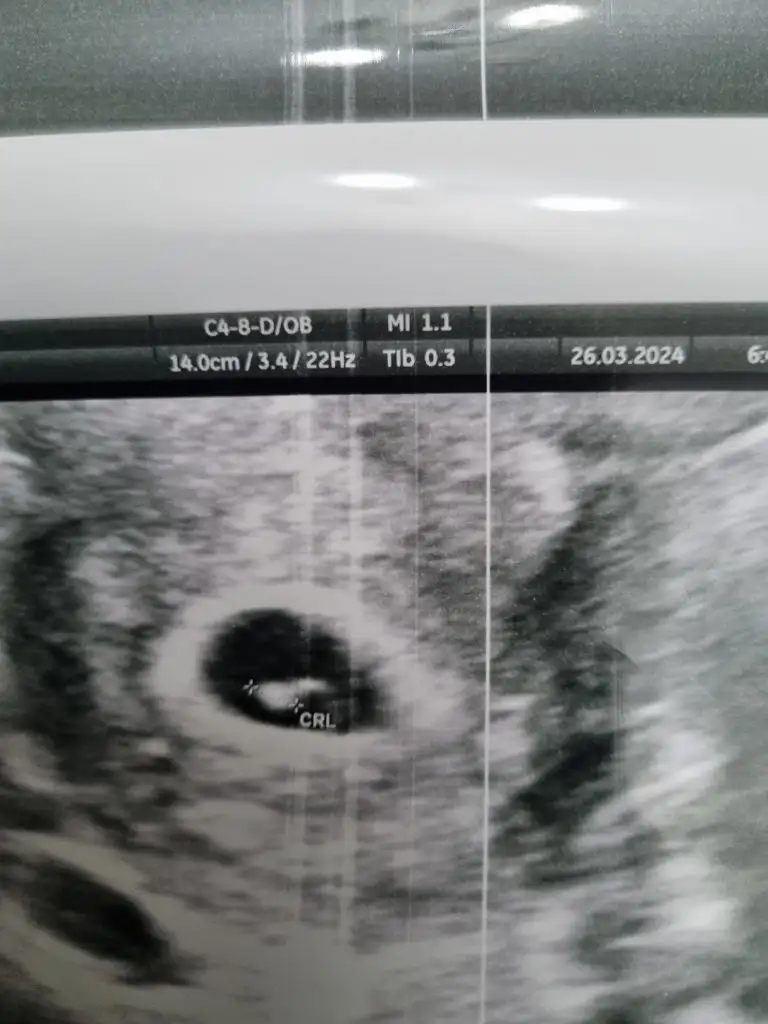

5 ve 14. haftaya kadar olan ultrason fotolarınızı paylaşın. Vajinadan mı yoksa karından mı çekildiğini ve kaç haftalık olduğunu da mutlaka belirtin.